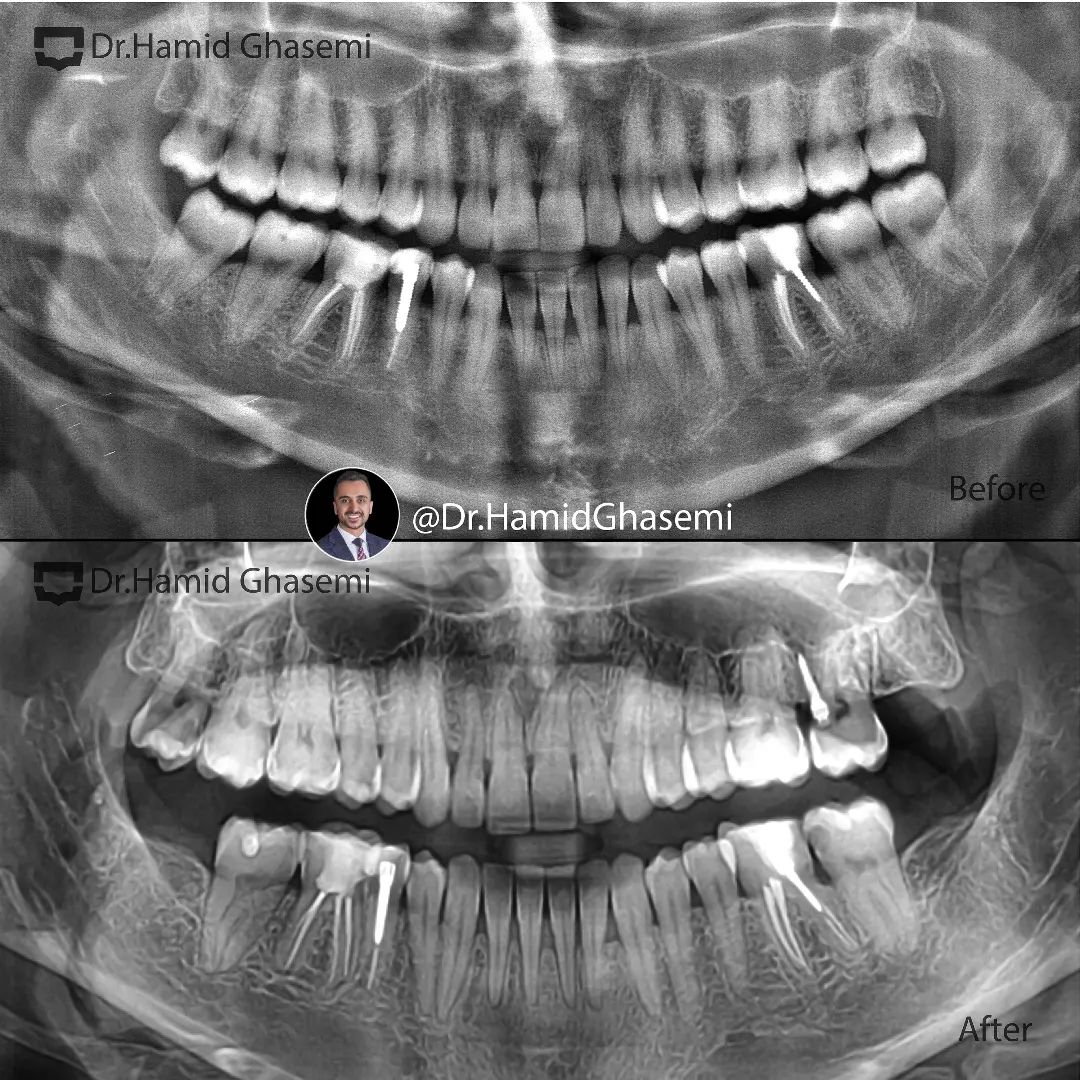

درمان ارتودنسی بدون جراحی فک در کیس کلاس ۳ با جلوزدگی فک پایین و انحراف فک بالا.

Non surgical orthodontic treatment of class 3 case with prognathic mandible and upper arch deviation